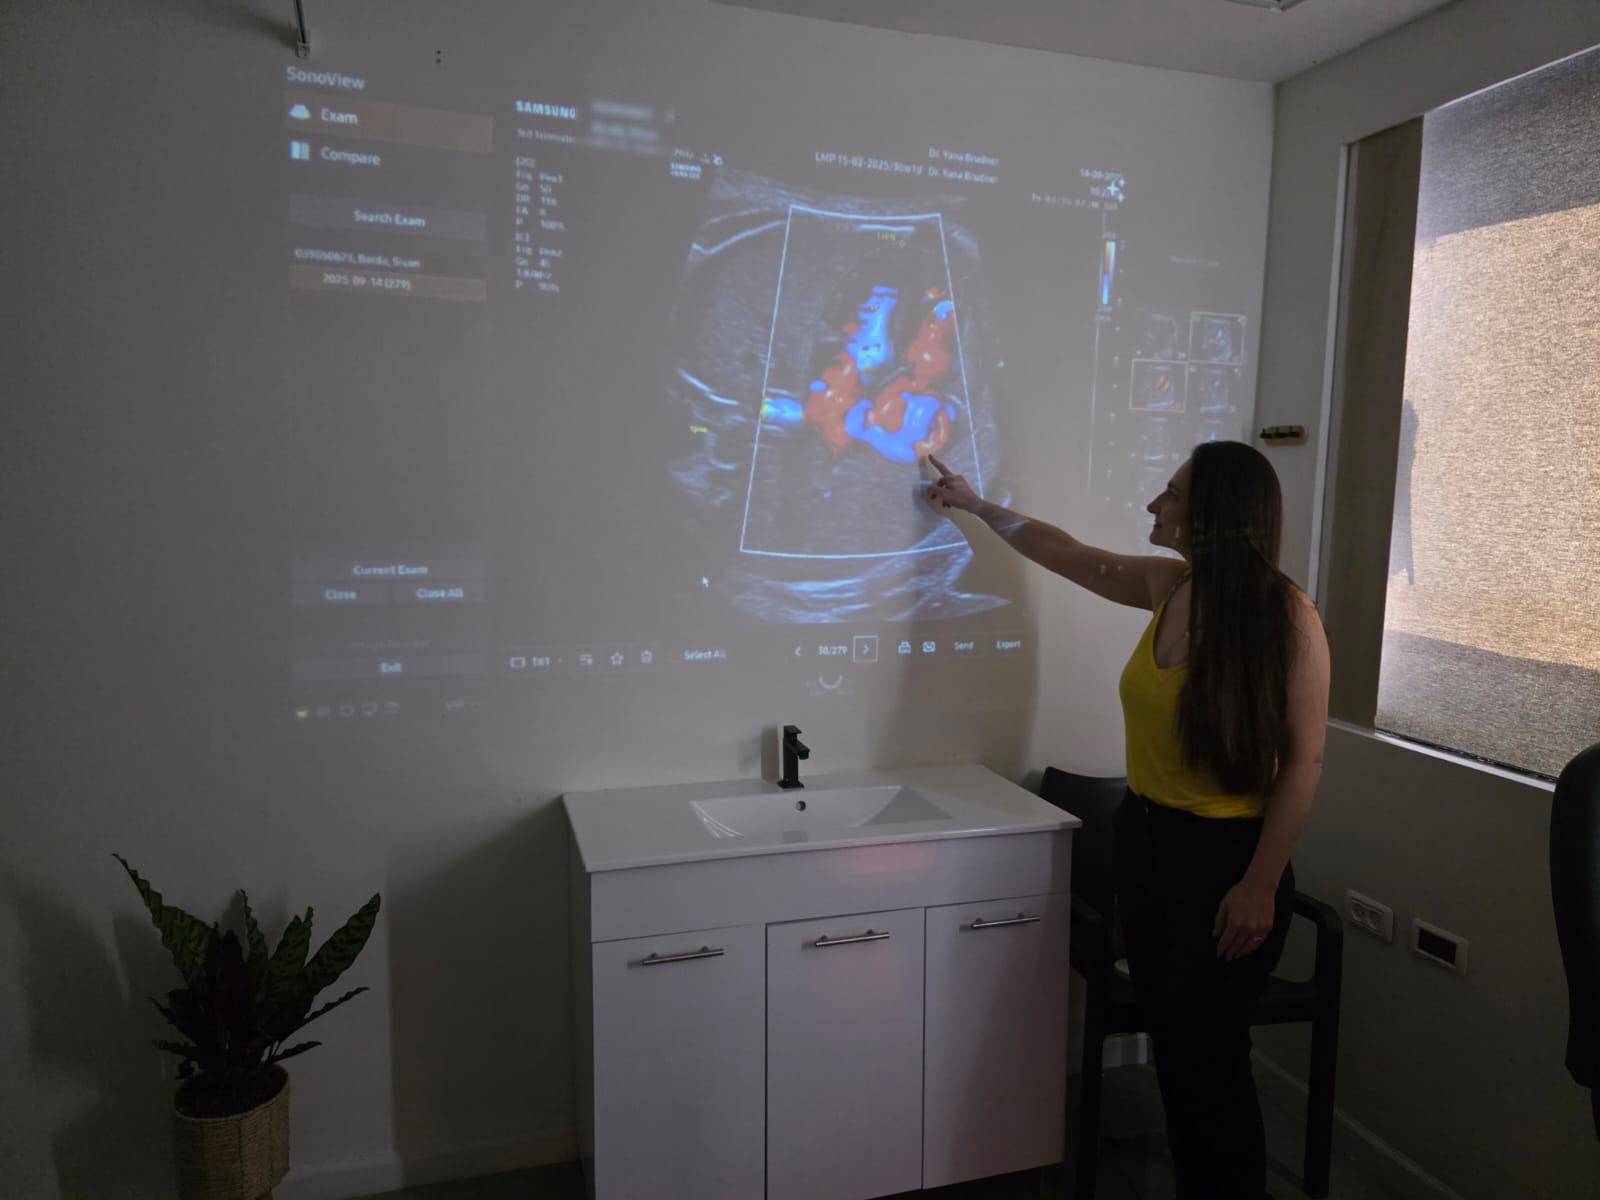

כאישה בהריון, אחת הבדיקות החשובות ביותר שעומדות לרשותי היא סקירת המערכות. זוהי בדיקת אולטרסאונד מקיפה

כאשר אני פוגשת נשים בהריון, אחת השאלות הראשונות שעולות היא לגבי משמעות בדיקת השקיפות העורפית.

בדיקת אולטרסאונד של התפתחות העובר בשליש השלישי היא אחת הבדיקות שמעניקות הרבה שקט להרבה נשים